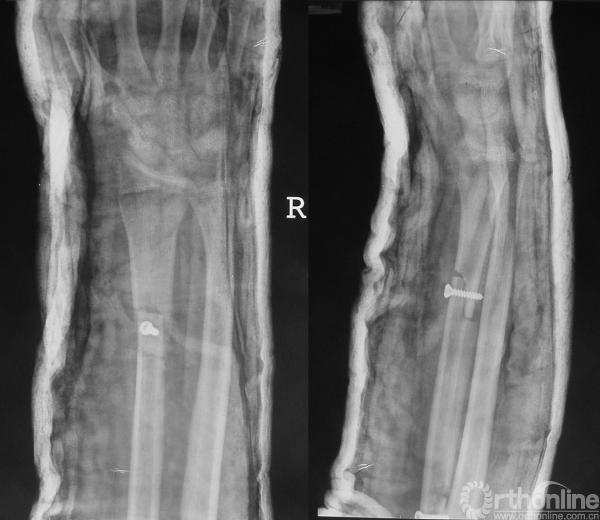

于当地医院就诊,诊断为“病理性骨折”,在未行术前活检的情况下,行“瘤段切除、腓骨移植术”。术后病理示“浸润灶和新生软骨、未见恶性肿瘤成分”。临床据此未予进一步治疗,随诊。

图14-2 术后X线平片正侧位

图14-3 术后2月X线平片正侧位

1.病理骨折诊断成立,但肿瘤性质未明确。以病史来看,短时间内出现复发,临床考虑侵袭性肿瘤可能性大,但病理并不能给予足够支持。这种情况可见于取材区域的不典型性或病理医生对骨肿瘤病理的认知不足。

2.仍然应该进行细致的影像学检查如局部加强CT来判断肿瘤的侵犯范围。